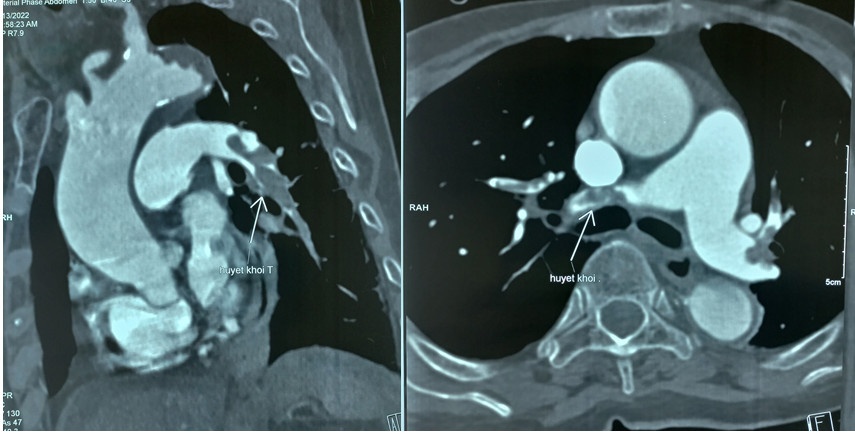

Bệnh nhân sốc tim do thuyên tắc động mạch phổi cấp hai bên (mũi tên chỉ vị trí cục máu đông). Ảnh: BVCC.

Theo PGS.TS Nguyễn Đình Tiến, Chủ nhiệm bộ môn Nội Hô hấp, bệnh nhân có thể bị tổn thương mạch máu nhỏ ở phổi, mắc huyết khối lớn và nhỏ đã xảy ra ở giai đoạn sớm của Covid-19. Hiện tượng này xảy ra ở Covid-19 nhiều hơn các bệnh virus khác. Mặt khác, tình trạng tăng đông có thể kéo dài qua thời kỳ hậu Covid-19.

Khi bệnh nhân có các biểu hiện như khó thở, đau tức ngực, ho và có thể ho ra máu, cần xét nghiệm D-dimer và kiểm tra X-quang phổi, điện tim, siêu âm tim. Nếu nghi ngờ thuyên tắc động mạch phổi, người bệnh cần chụp CT-Scan ngực có thuốc cản quang để chẩn đoán xác định huyết khối động mạch phổi.